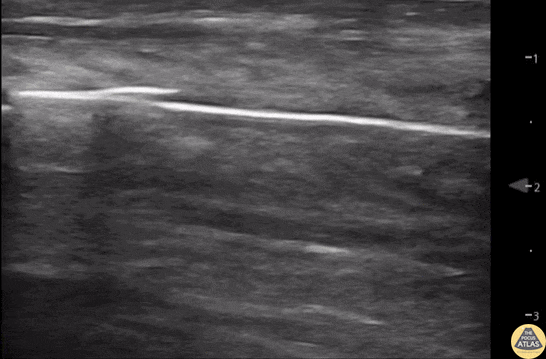

Musculoskeletal - Normal Knee US in TKA Patient

55 yo F s/p RT TKA w/ revision presents after a fall. POCUS was w/o tendinous/bony abnormality. RT knee x-ray was w/o definite acute fracture. The American College of Radiology (ACR) promotes US evaluation of “pain after...(TKA with) suspect(ed) periprosthetic soft-tissue abnormality unrelated to infection” after radiographic evaluation as “usually appropriate”. Although ACEP US Guidelines boast 96.8% sensitivity and 99.7% specificity for diagnosing fractures, POCUS evaluation of traumatic arthroplasty complications does not exist. This creates an area of interest within POCUS. Contributors: Lauren Lowes, DO; Justin Morin, DO; Garrett Richardson, MS4; Nava Kendall, MD Central Michigan University Residency of Emergency Medicine